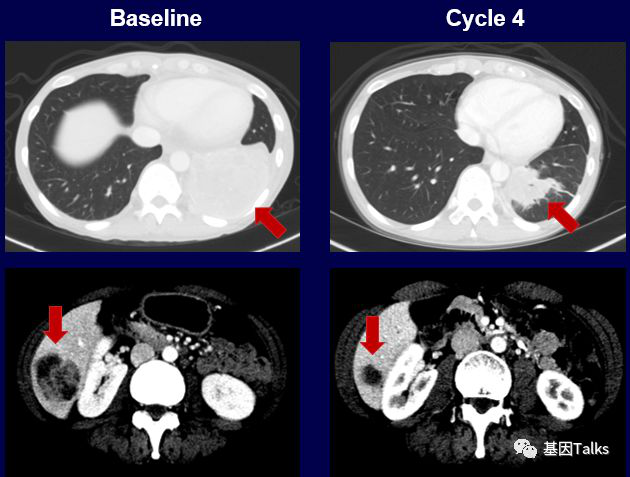

(1)1例肺癌合并SQSTM1-NTRK1融合:

上图上半部分,这位耐药患者尝试LOXO-195新药后,肿瘤再次快速缩小,用药4周后,肿瘤负担减少了38%,继续治疗显示肿瘤负担减少了58%。